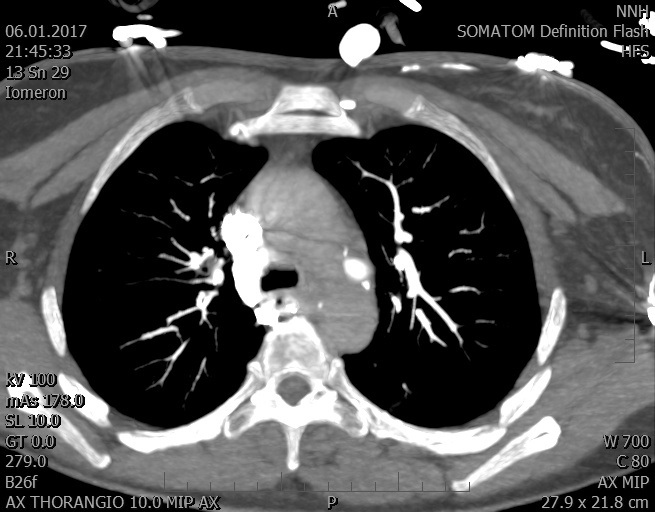

Video 2 - Echokardiograficky byla zjištěna těžká dysfunkce dilatační levé komory s nezvětšenou pravou komorou.Pro nejasnou příčinu zástavy jsme provedli i vyšetření výpočetní tomografií (CT), které vyloučilo plicní embolizaci (série 1 - soubory na konci článku). V den přijetí při přetrvávající oběhové nestabilitě byla nemocná opakovaně defibrilována pro fibrilaci komor se stabilizací rytmu po podání amiodaronu a mesocainu. Dle hemodynamických měření se jednalo o těžký kombinovaný šok. Vstupní laboratorní vyšetření bylo bez větších pozoruhodností. Posléze jsme doplnili anamnézu od příbuzných a zjistili, že pacientka užila do dvou hodin před srdeční zástavou první tabletu amoxicilinu na lehký respirační infekt. Při nevýtěžnosti vstupních vyšetření a nových anamnestických informacích jsme doplnili 14 hodin po kolapsu vyšetření koncentrace tryptázy v séru, která byla extrémně zvýšena (tabulka 2), což nás vedlo k podezření na anafylaxi.